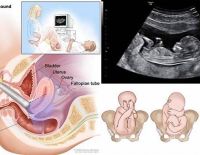

Thai 7 tuần siêu âm bụng hay đầu dò là tốt nhất cho mẹ bầu?

Để trả lời câu hỏi “Thai 7 tuần siêu âm bụng hay đầu dò?” thì trước hết, mẹ cần biết rõ về ưu nhược điểm của hai dạng siêu âm phổ biến này. Theo tư vấn của bác sĩ chuyên khoa II, loại hình siêu...

Tác dụng của siêu âm đầu dò âm đạo và những điều cần biết

Siêu âm đầu dò âm đạo là kỹ thuật giúp kiểm tra và nhận định chính xác tình trạng sức khỏe sinh sản của nữ giới. Đồng thời có thể nhận biết được việc mang thai ngoài tử cung, các khối u bên trong. Vậy...